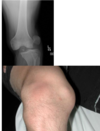

normal knee x-ray